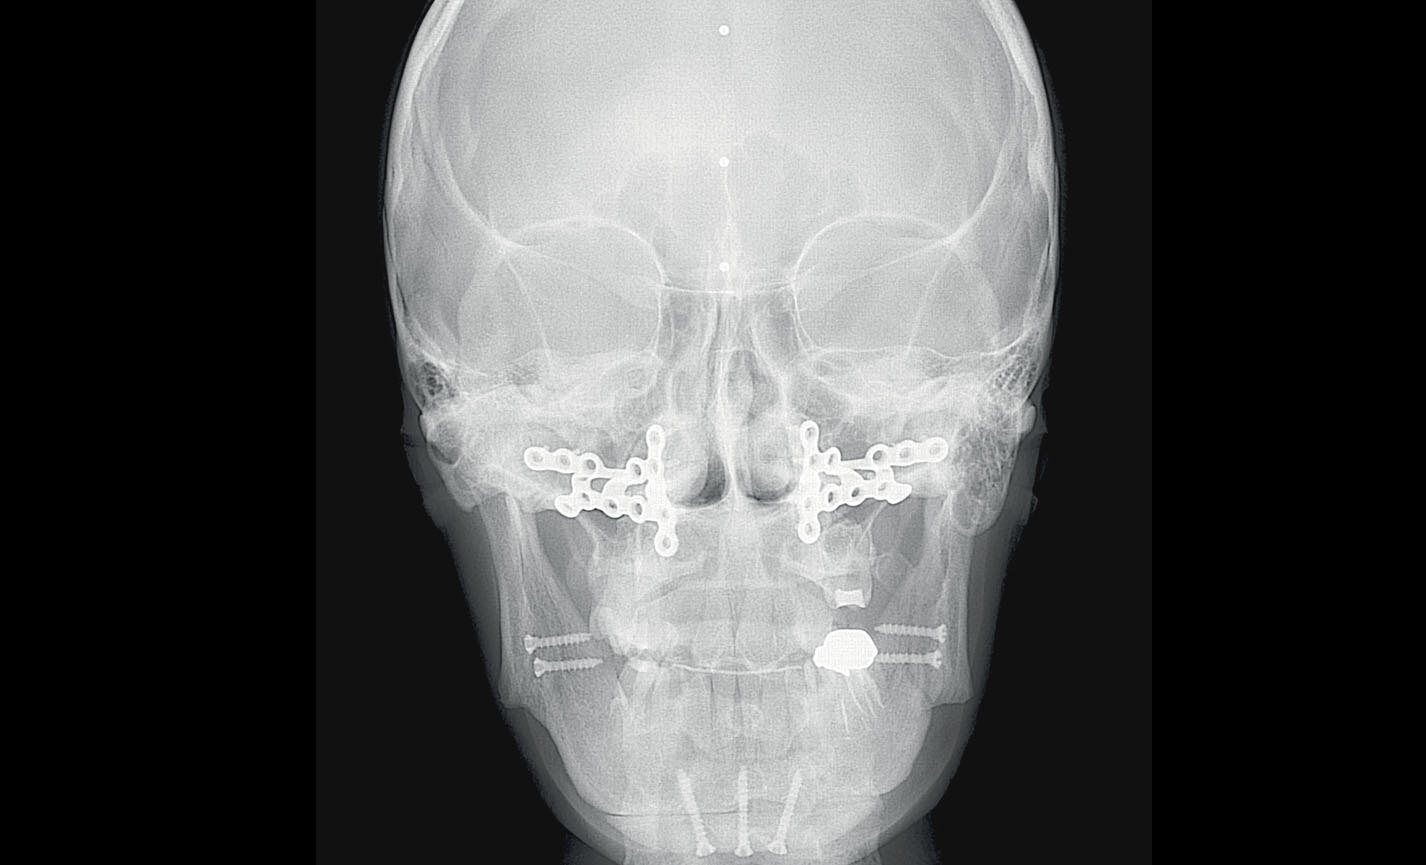

3D SMART

La fonction intelligente 3D SMART (Streak Metal Artifacts Reduction Technology) permet de réduire les artéfacts métalliques sur les images 3D, avec une procédure complètement automatique. Rendez vos images volumétriques toujours exploitables, même en présence d’implants et de restaurations en amalgame.